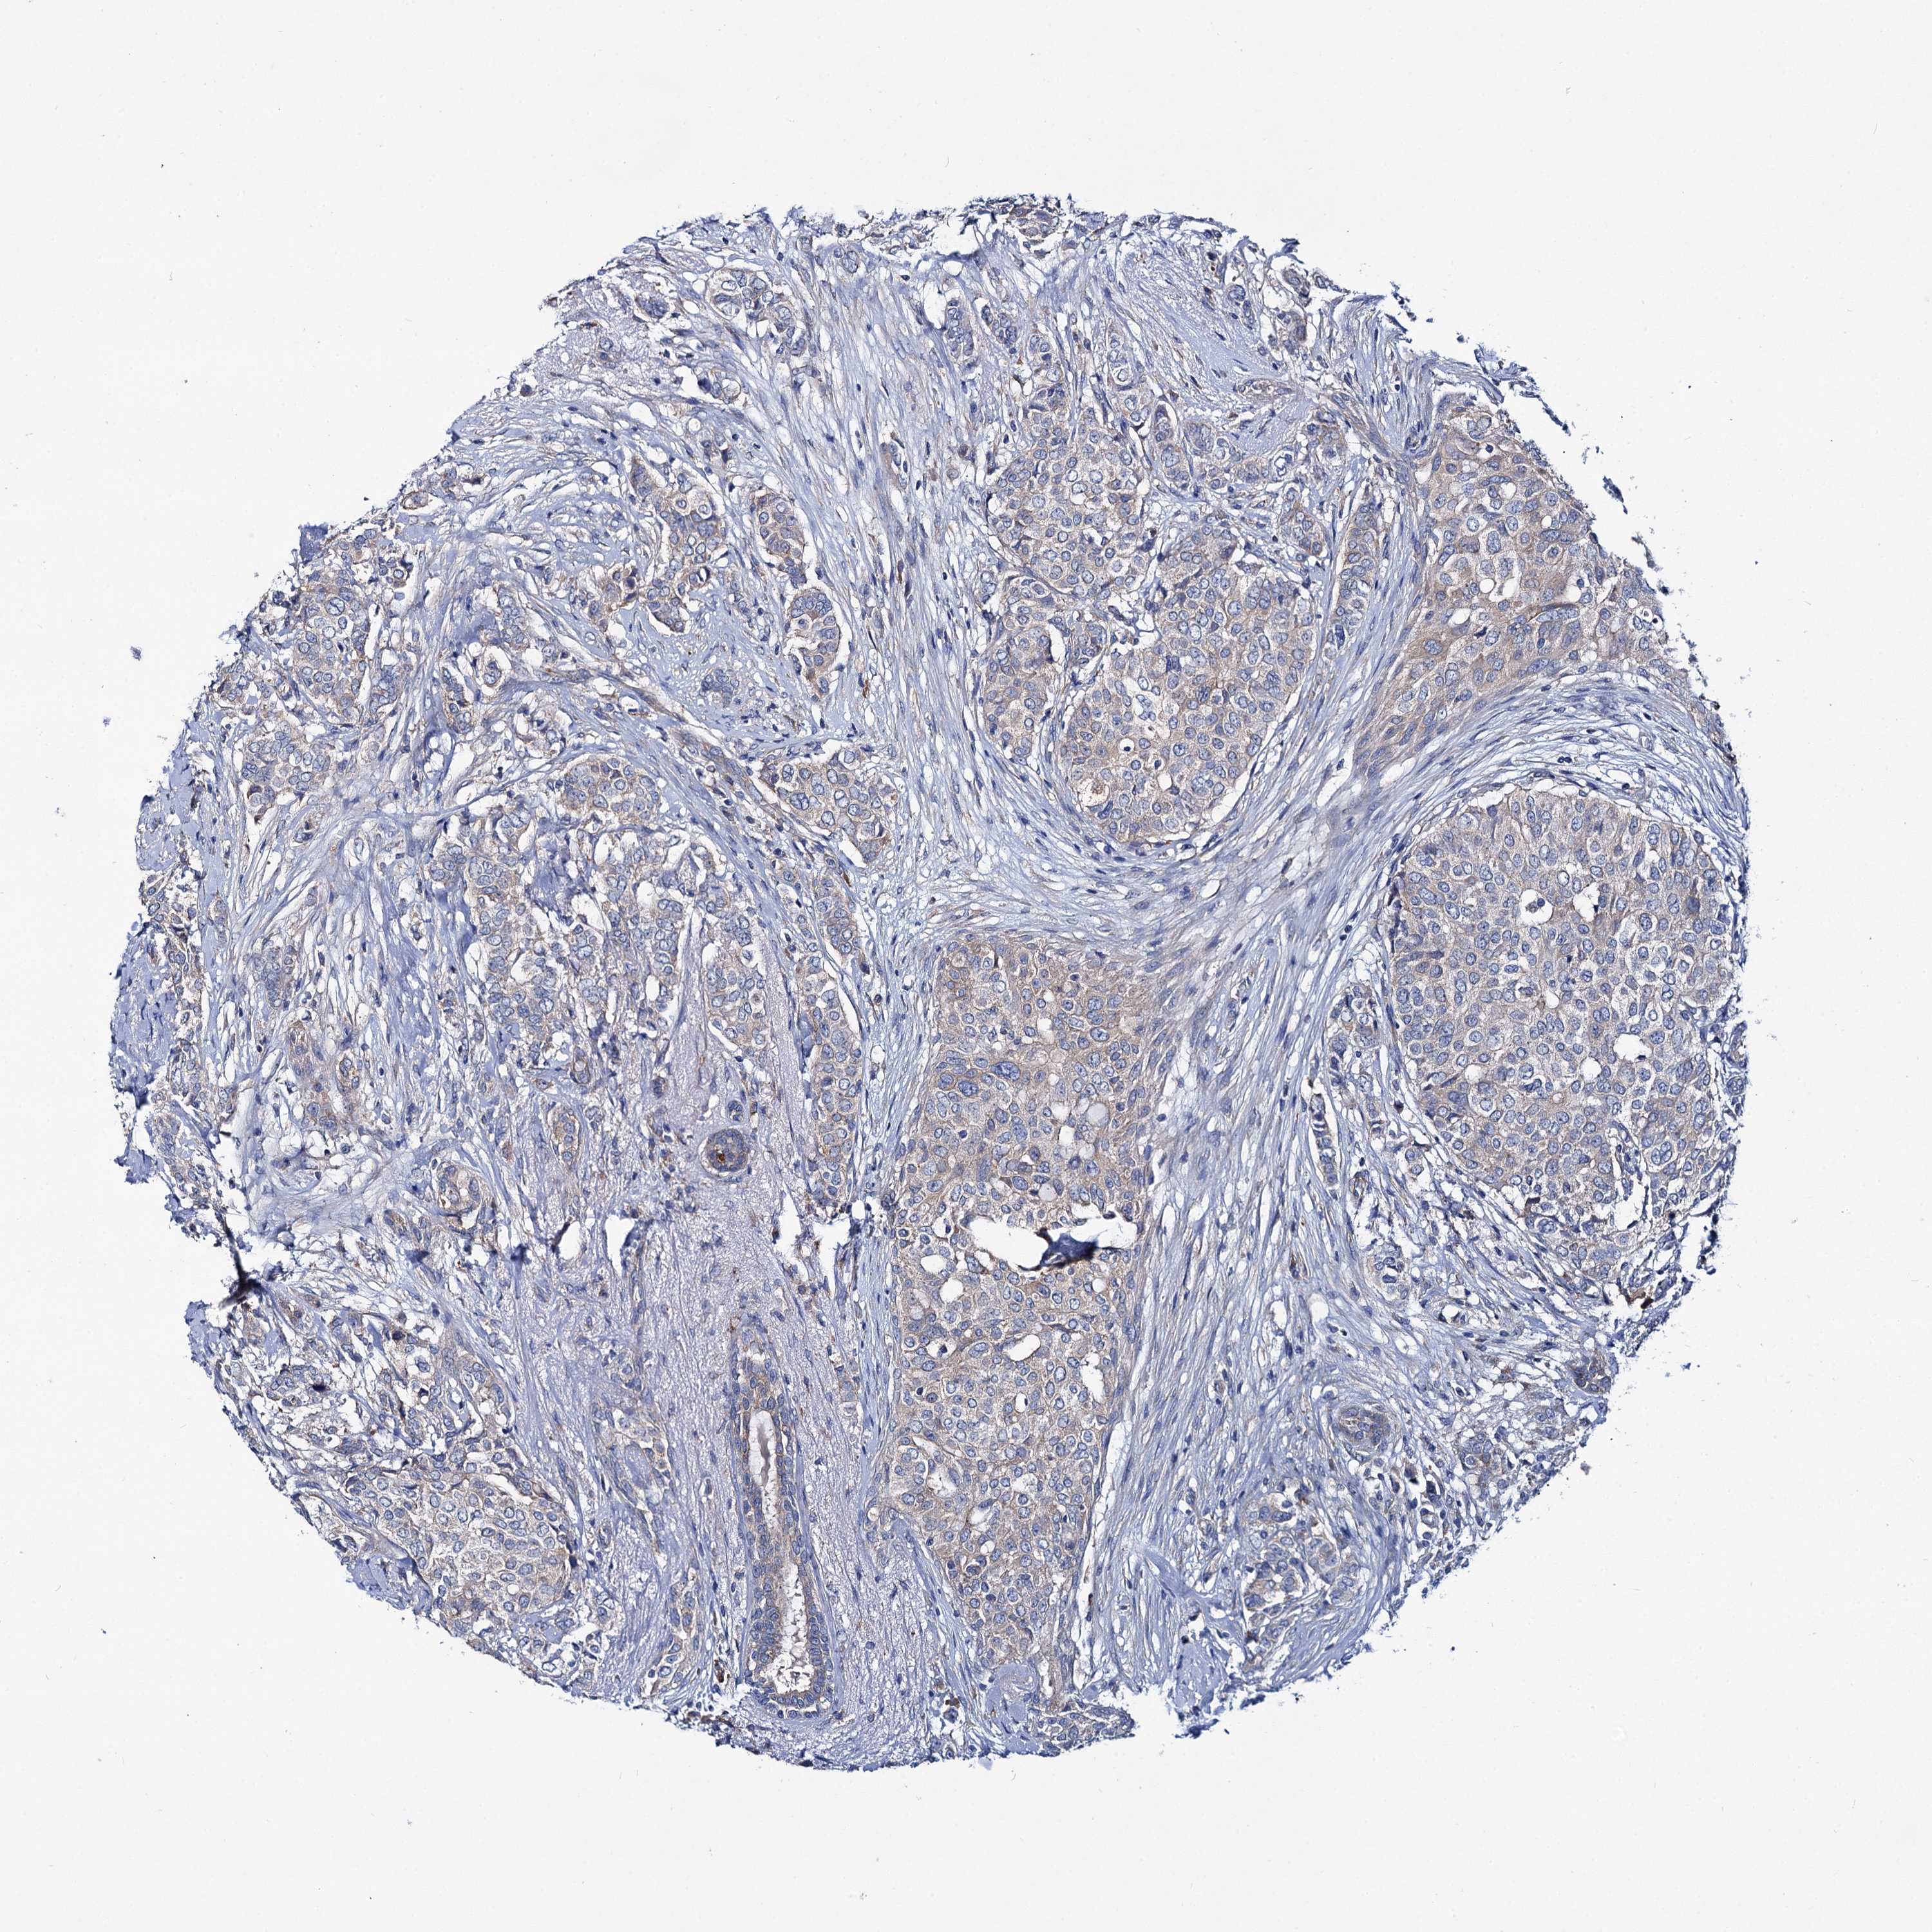

CANCER BREAST CANCER Show tissue menu

BRCA TCGA BRCA VALIDATION PROTEIN EXPRESSION

ANTIBODIES

AND

VALIDATION